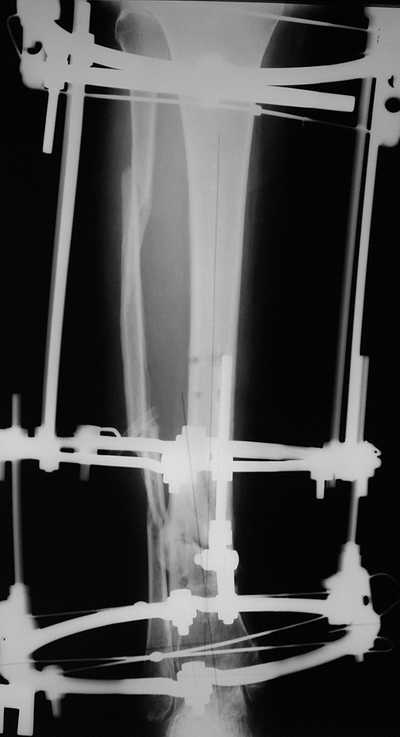

Мужчина, 33 года, резекция б\б кости по поводу остеомиелита после открытого перелома. Стандартная методика билокального остеосинтеза (рис 1 и 2). В конце удлинения выявилось неудовлетворительное взиморасположение перемещенного фрагмента и дистального отломка (рис 3). Планирование (рис 4).

Адаптация отломков гексаподом за 5 дней (рис 5). Замена гексапода на обычные штанги (рис 6 и 7)